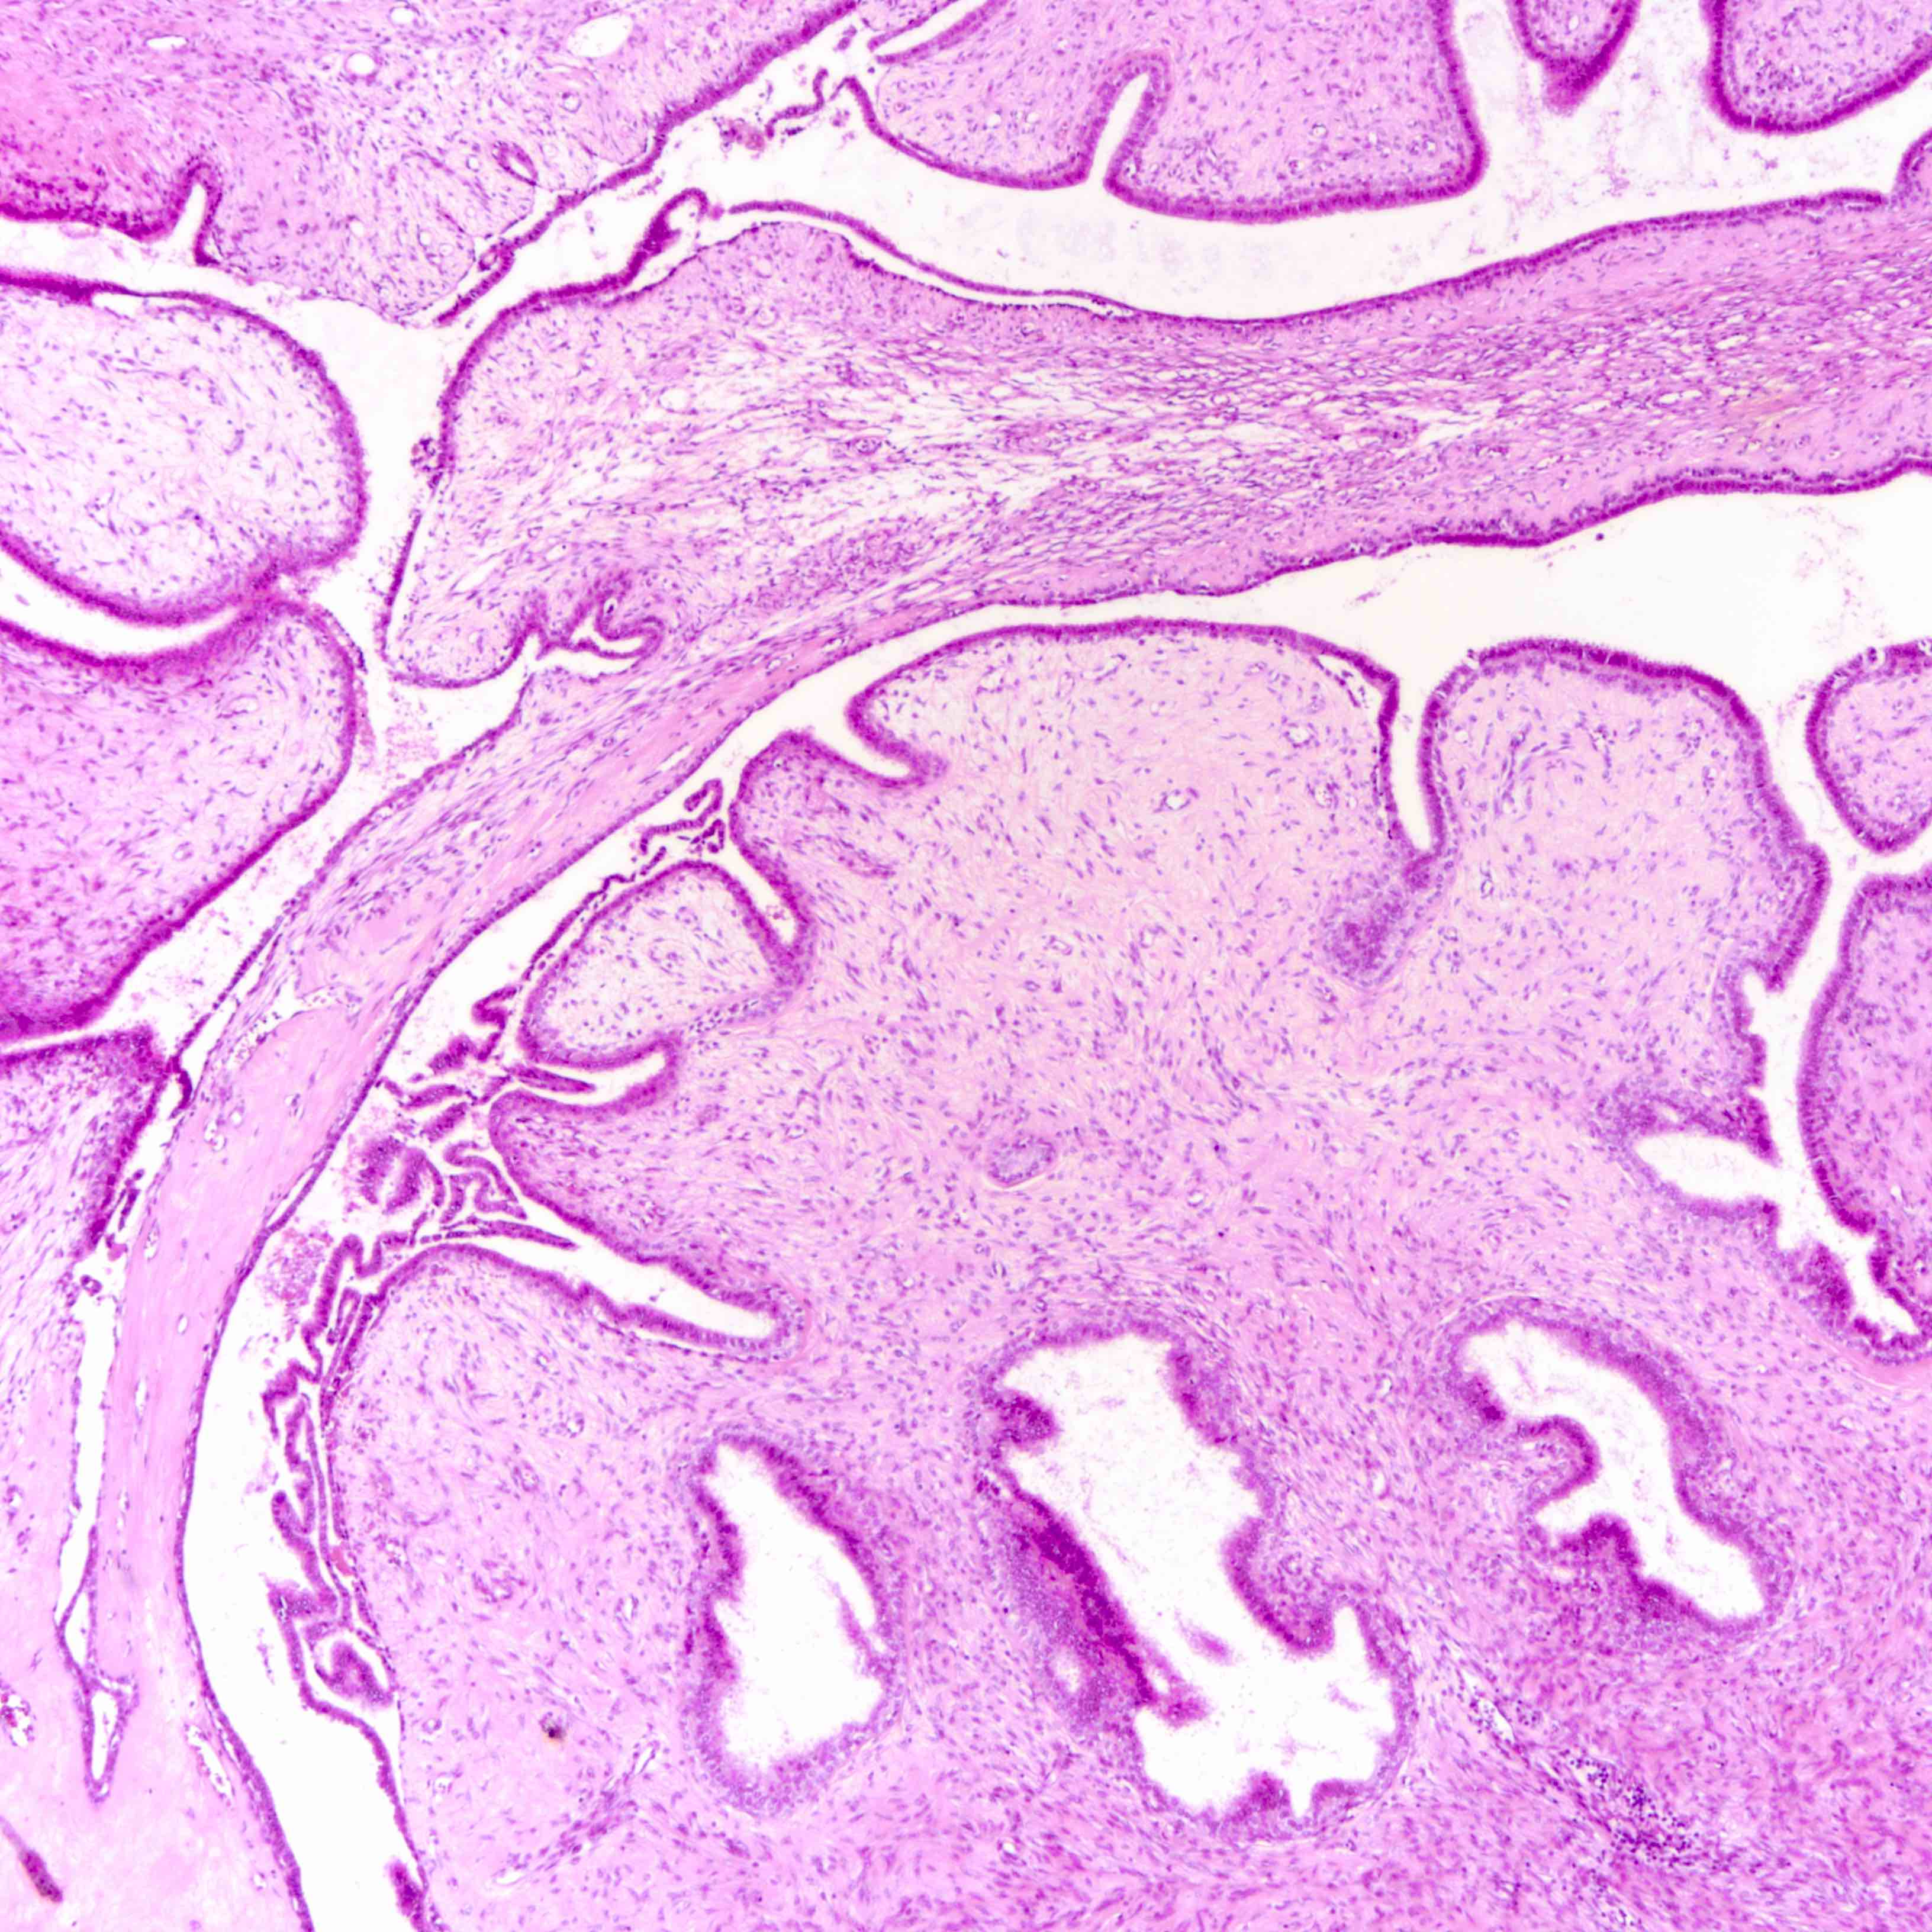

Microscopic (histologic) images

Contributed by Joshua J.X. Li, M.B.Ch.B. and Gary M. Tse, M.B.B.S.

Borderline phyllodes tumor

Malignant phyllodes tumor